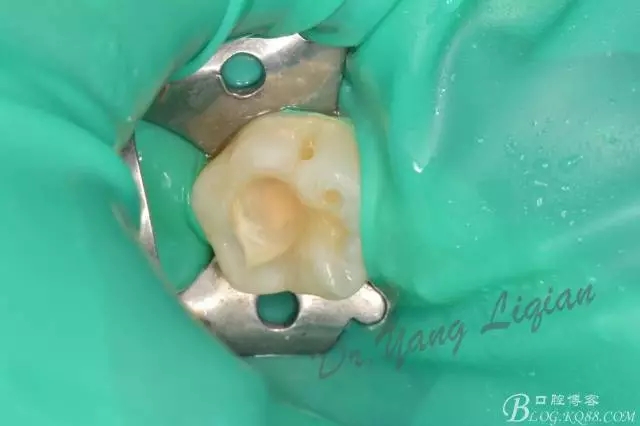

高嵌體&樹脂充填病例

高嵌體一例

樹脂充填一例